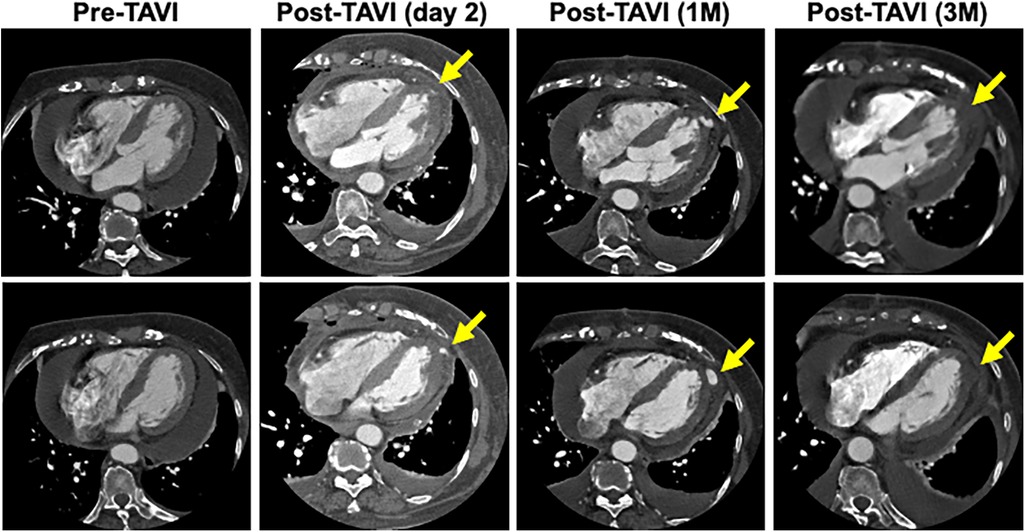

A blood test obtained one day after TAVI revealed marked elevation of myocardial enzymes: creatine kinase (CK) at 1921 U/L and CK-MB at 236 U/L. Despite these findings, the patient did not report chest pain, and electrocardiography showed no ischemic changes such as ST-segment elevation or new Q waves. Given the absence of clinical and electrocardiographic evidence of acute myocardial infarction, alternative causes of enzyme elevation were considered. These included myocardial injury secondary to mechanical stress from the procedure itself, microvascular embolization, temporary guidewire-induced trauma, or global ischemia due to rapid pacing during valve deployment. Initial transthoracic echocardiography revealed no regional wall motion abnormalities. However, a repeat study performed three hours later identified new, localized hypokinesis at the left ventricular apex, although the volume of pericardial effusion remained unchanged. To further investigate, contrast-enhanced CT was performed five hours after the enzyme elevation was noted. This allowed us to confirm the presence of a pseudoaneurysm at the left ventricular apex. And, by color doppler echocardiography, we also confirmed abnormal flow within the newly visualized apical structure, consistent with a pseudoaneurysm that was seen in the CT scanning (Figure 3). Due to the findings of rapidly expanding of the pseudoaneurysm, and the extremely high potential risk of cardiac rupture, emergency surgical intervention was undertaken. Intraoperatively, a pseudoaneurysm measuring approximately 7 mm was identified on the lateral aspect of the left ventricular apex. The surrounding myocardial tissue was noted to be fragile, suggesting localized necrosis or structural compromise. Surgical repair was performed using two bovine pericardial patches (4 × 1 cm), which were sutured in place with continuous stitching. Postoperatively, the pseudoaneurysm cavity was largely thrombosed, and follow-up CT imaging demonstrated a reduction in the contrast-enhancing area to approximately 5 mm (Figure 4). One month later, repeat CT imaging showed no residual aneurysmal structure. She was transferred from the intensive care unit on postoperative day 9 and discharged from the hospital on day 27. She continues to do well on outpatient follow-up.

Figure 4. Time course of the morphology of the pseudoaneurysm. CT scan taken 3 months after repair surgery showed that the lumen of the pseudoaneurysm had disappeared.